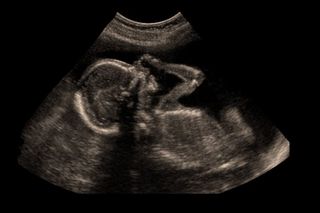

Yesterday, the Bombay High Court ruled to allow a 13-year-old survivor of rape to terminate her 24-week pregnancy.

The minor in question was kidnapped by her rapist from Kalyan, Maharashtra, in July of last year. The 23-year-old man had been working as a laborer in Kalyan, but, after abducting the girl, he took her to his village in Uttar Pradesh. In March of this year — eight months after being abducted — the girl was found by police and retrieved from the UP village. When the police took her for a medical examination upon returning her to Mumbai, she was found to be pregnant.

If this wasn’t upsetting enough, here’s where it gets crazy: When the police came to know about her pregnancy, they, for reasons known only to them, declined to tell the girl or her family that she was pregnant. At the time, she could have legally obtained an abortion, as her pregnancy had not crossed 20 weeks’ gestation, the legal threshold per India’s Medical Termination of Pregnancies Act. (Of the countries that allow abortion, many have a legal limit that falls between 20 and 24 weeks; some, like the United States, have provisions for late terminations, typically when “necessary to preserve the life or health of the woman.”)

When the girl and her family learned of the pregnancy, they were barred from terminating it because she had already crossed the gestational limit. Her father then filed a petition appealing to the High Court to allow the abortion.